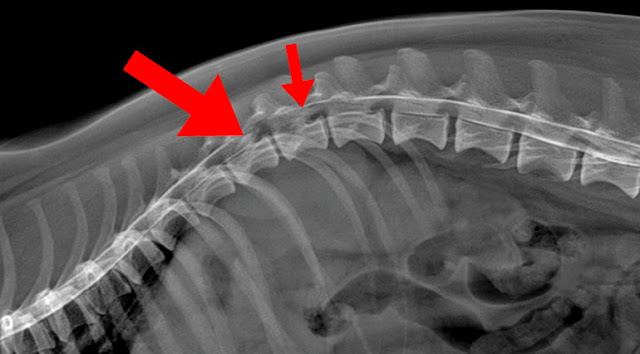

La exploración veterinaria incluirá un examen neurológico completo, lo que ayudará a emitir un juicio clínico sobre la localización y gravedad de la lesión. Las radiografías simples pueden mostrar un área anormal en la columna vertebral, sin embargo, son necesarias pruebas más sensibles como un TAC (tomografía axial computerizada) o una resonancia magnética para determinar el grado y lugar de la compresión, además de ayudar a encaminar el cuadro hacia un tratamiento quirúrgico o conservador.